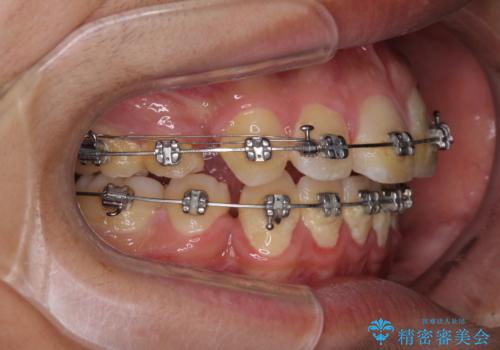

- メタルブラケット

- 治療期間

- 2年10ヶ月

- 治療回数

- 10-30回

小学生の頃に上顎前歯をぶつけ、歯の一部が破損している状態であったので、歯根が歯槽骨と癒着して移動しない可能性がありましたが、無事に治療を終えることができました。

受験勉強と重なり、舌のトレーニングが十分に行えず、高校生としてはやや長期間の治療となりました。